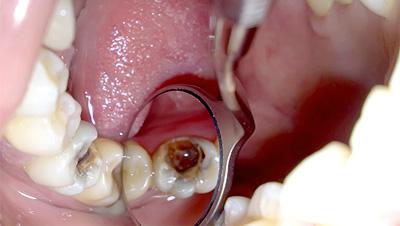

Удаление пульпы, разрушенного моляра и клыков

Для разных зубов свои особенности экстракции. Удаление пульпы (внутренней зубной полости) производится одним из двух способов:

- Ампутация, то есть удаление лишь коронковой части пульпы. Ампутации подвергаются только многокорневые зубы с корнями правильной формы.

- Экстирпация, то есть полное удаление пульпы.

Важно! Депульпированный зуб лишается нерва и не может болеть, но некоторые пациенты жалуются на ноющие боли в области зуба, подвергшегося лечению. По мнению специалистов, боль может держаться около двух месяцев. Если болевые ощущения продолжаются свыше двух месяцев, пациенту рекомендуется обратиться к врачу.

Удаление разрушенного постоянного зуба производится либо простым, либо хирургическим способом. Особенность процедуры заключается в том, что зубы на верхней челюсти удалить сложнее, чем на нижней, так как на верхней челюсти стенки лунок длиннее и толще.